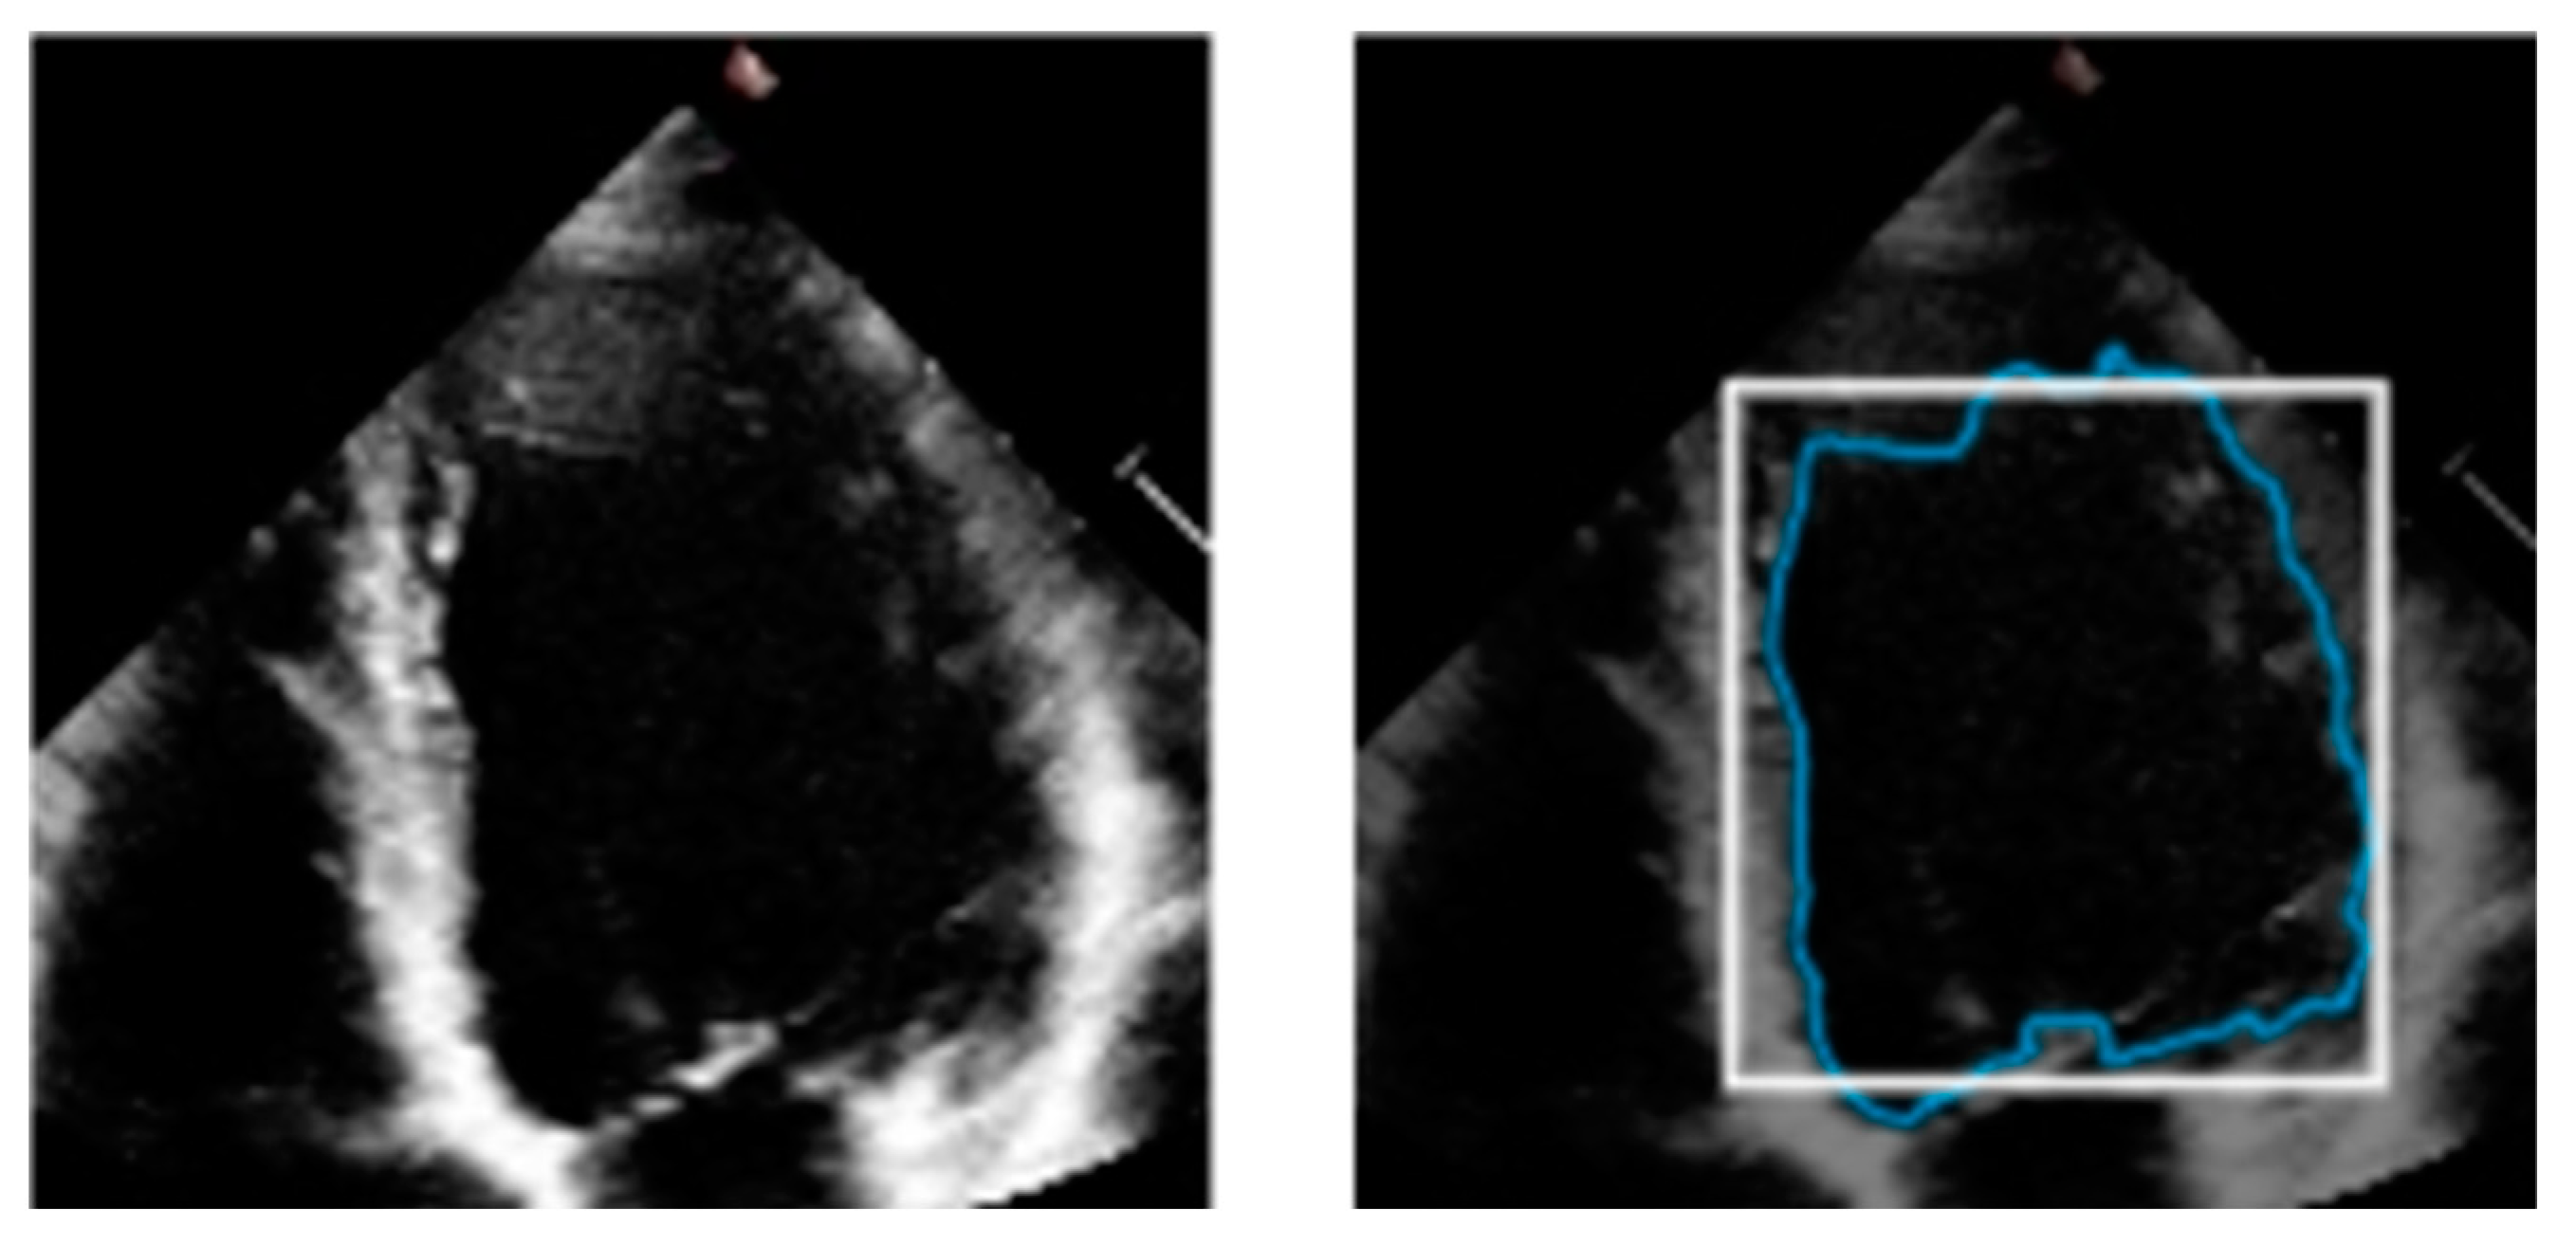

Various medical imaging modalities have been utilized to evaluate the LV, and due to improvements in these medical imaging methods, it is now easier to diagnose cardiovascular problems. For example, echocardiography creates cardiac anatomical images using ultrasound (US) waves with high frequencies. Moreover, ultrasound is indispensable for assessing LV function due to its ease of access, exceptional temporal resolution, non-invasiveness, and real-time execution [3]. An example of a two-dimensional US image is shown in Figure 1, wherein the blue track indicates the LV boundary, which is an example output of manual segmentation. A specialist, usually a cardiologist, very meticulously segments the endocardial border of the LV at the end-systolic and end-diastolic phases. This information is then used to offer a quantitative functional examination of the heart in order to identify cardiopathies.

Figure 1.

US image (left) and its US image with LV boundary (right).